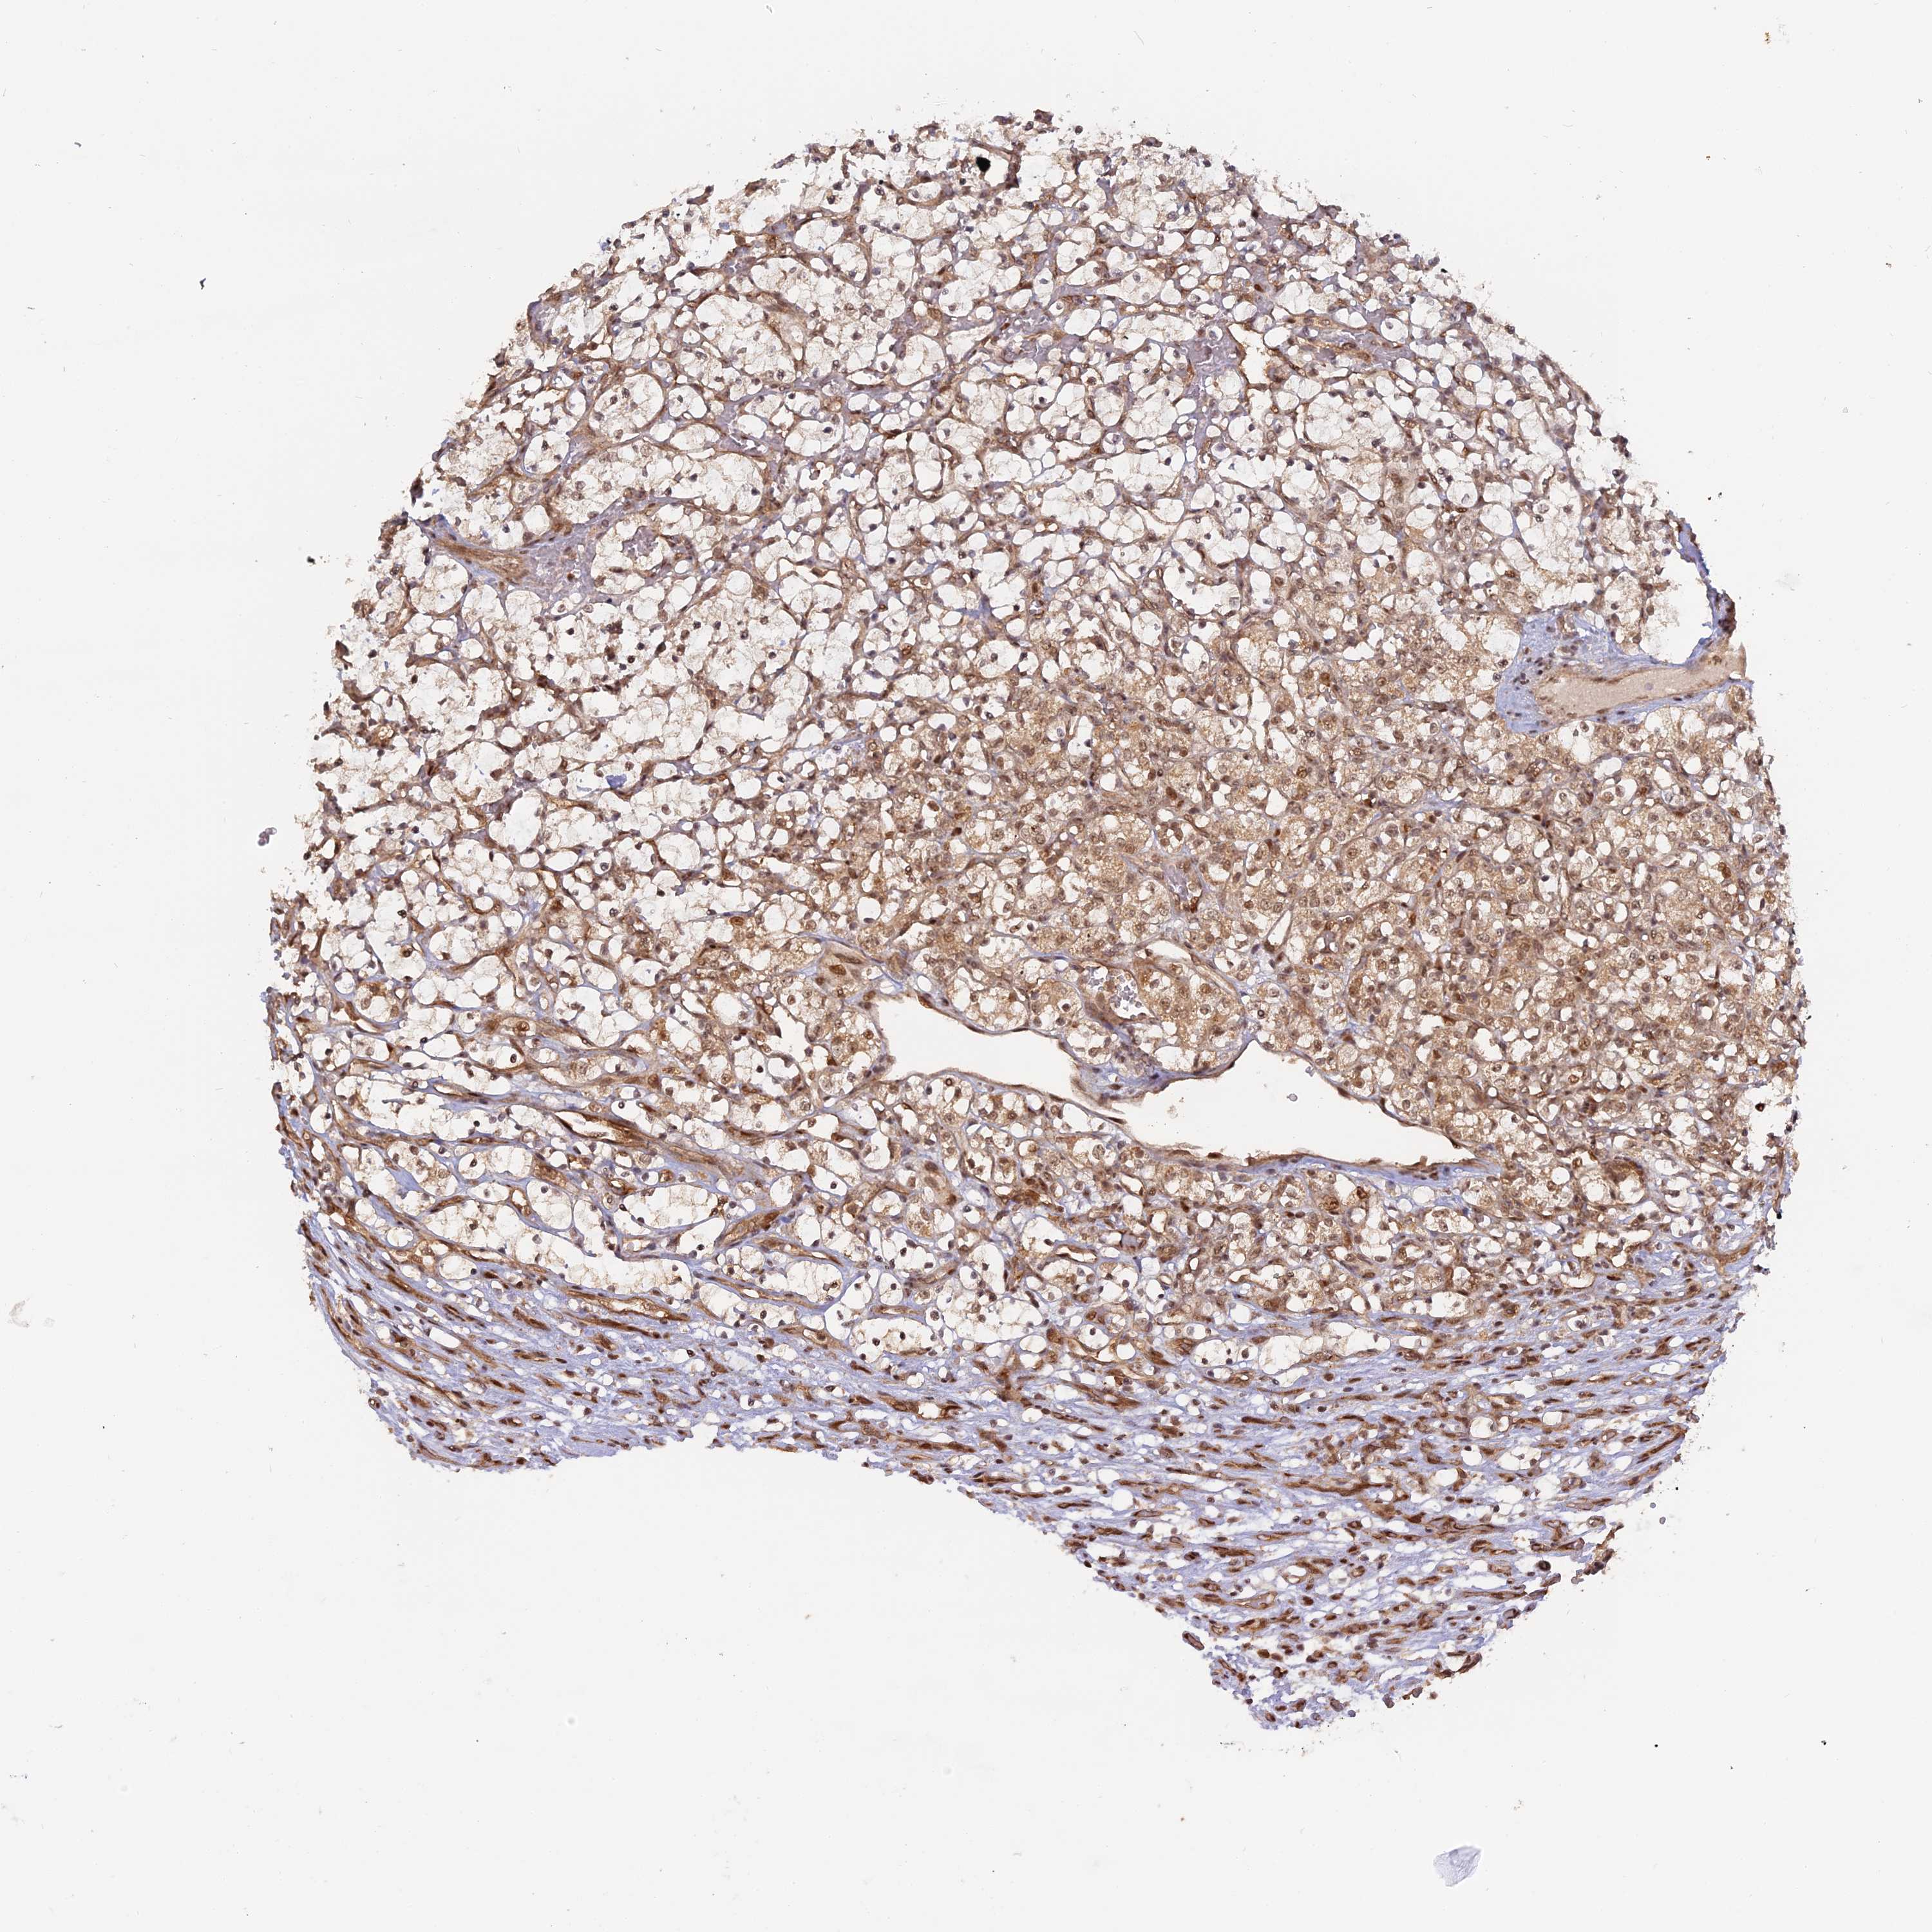

KIDNEY RENAL CLEAR CELL CARCINOMA (VALIDATION) - Interactive survival scatter ploti

The Survival Scatter plot shows the clinical status (i.e. dead or alive) for all individuals in the patient cohort, based on the same data that underlies the corresponding Kaplan-Meier plots. Patients that are alive at last time for follow-up are shown in blue and patients who have died during the study are shown in red.

The x-axis shows the expression levels (FPKM) of the investigated gene in the tumor tissue at the time of diagnosis. The y-axis shows the follow-up time after diagnosis (years). Both axes are complimented with kernel density curves demonstrating the data density over the axes. The top density plot shows the expression levels (FPKM) distribution among dead (red) and alive patients (blue). The right density plot shows the data density of the survived years of dead patients with high and low expression levels respectively, stratified using the cutoff indicated by the vertical dashed line through the Survival Scatter plot. This cutoff is automatically defined based on the FPKM cutoff that minimizes the p-score. The cutoff can be changed by dragging the vertical line or by entering a cutoff value in the square labeled "Current cut-off".

Under the Survival Scatter plot the p-score landscape (black curve; left axis) is shown together with dead median separation (red curve; right axis). Dead median separation is the difference in median mRNA expression between patients who have died with high and low expression, respectively. It is calculated as follows: median FPKM expression of dead patients with high expression - median FPKM expression of dead patients with low expression. This is intended to aid the user in visually exploring custom cutoffs and the associated p-scores and dead median separation.

Individual patient data is displayed and can be filtered by clicking on one or more of the category buttons on the top of the page. Categories describing expression level and patient information include: high, low, alive, dead, female, male and tumor stages. The scale of the x-axis can be toggled between linear and log-scale by clicking on the "x log" button. Mouse-over function shows TCGA ID, patient information and mRNA expression (FPKM) for each patient.

& Survival analysisi

Kaplan-Meier plots summarize results from analysis of correlation between mRNA expression level and patient survival. Patients were divided based on level of expression into one of the two groups "low" (under cut off) or "high" (over cut off). X-axis shows time for survival (years) and y-axis shows the probability of survival, where 1.0 corresponds to 100 percent.

PKIG is validated prognostic, high expression is favorable in Kidney Renal Clear Cell Carcinoma (validation)

Best expression cut offi

Based on the FPKM value of each gene, patients were classified into two groups and association between prognosis (survival) and gene expression (FPKM) was examined. The best expression cut-off refers the FPKM value that yields maximal difference with regard to survival between the two groups at the lowest log-rank P-value. Best expression cut-off was selected based on survival analysis .

When clicking on this number, the vertical dashed line indicating cut-off, the interactive survival plot, and the Kaplan-Meier curve will be adjusted to show results based on the best expression cut-off.

: 80.9

Average pTPM 86.4

Number of samples 100